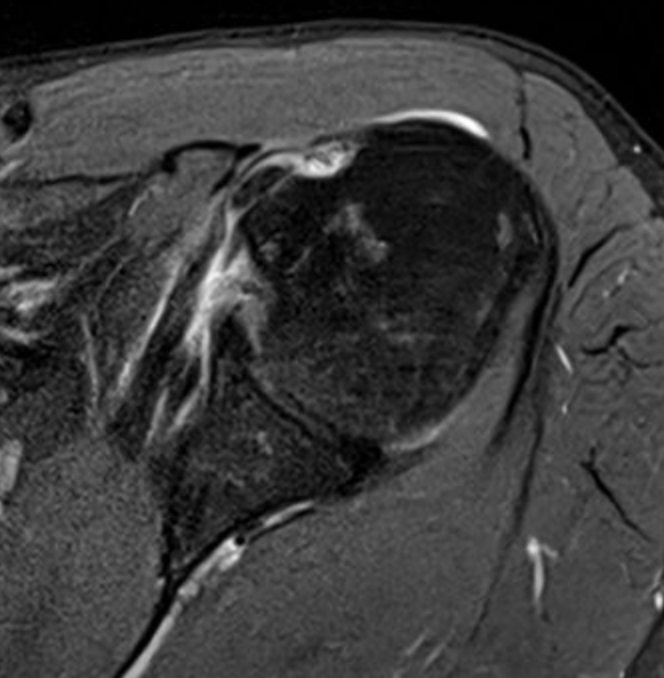

Medial subluxation with subscapularis tear